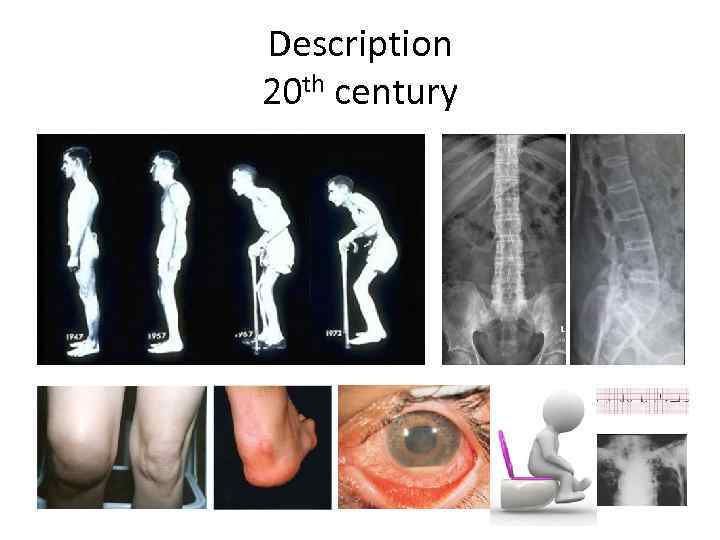

Description 20 th century

Patient’s symptoms One half comes from inflammation, the second half comes from structural changes

Arthritis

Enthesopathy

Uveitis

Aortitis